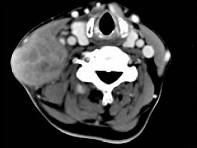

问题 65岁男性,吸烟史30余年,近半年来颈部出现疼痛性肿块,CT扫描如图所示,请选择最可能诊断()

选项 A.淋巴结核 B.血管瘤 C.神经鞘瘤 D.淋巴结转移瘤 E.软组织脓肿

答案 D